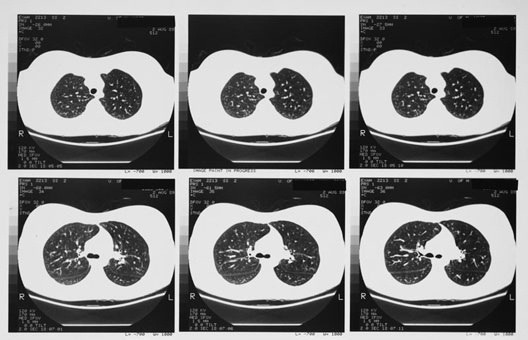

Radiology Images

Lung CT

1. Right lung

2. Trachea

3. Left lung

4. Bifurcation

5. Right bronchus

6. Left bronchus